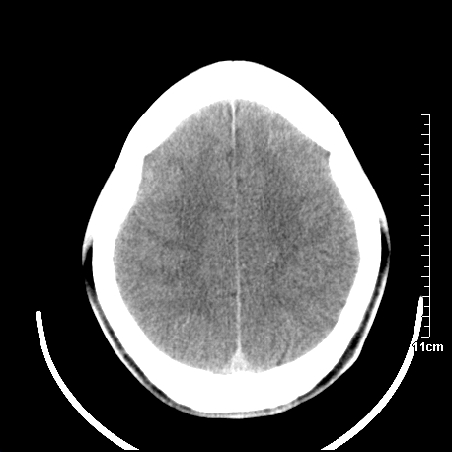

头晕.头痛间断意识恍惚1周 m/21y

4天上述症状加重伴左侧肢体发软,复查ct,

右側放射冠区改变,建议ct增强或mri检查.

右側额叶、放射冠区灰白质改变,建议ct增强或mri检查

右侧基底节区低密度灶,建议磁共振检查。

右侧放射冠区混杂密度灶,边缘不清,病人较年轻,结合有发热病史,支持感染性病变,建议密切结合临床可抗感染治疗后复查。

右侧颞叶混杂密度灶,强烈建议:增强ct检查